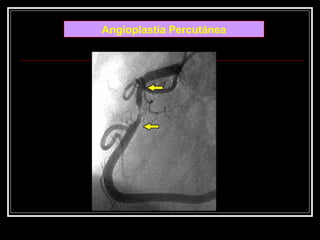

 Arteria coronaria

derecha

 lesión crítica en su

tercio medio con

imagen de trombo

en su interior

Angioplastía Percutánea

 Arteria coronaria derecha lesión crítica en su tercio medio con imagen de trombo en su interior